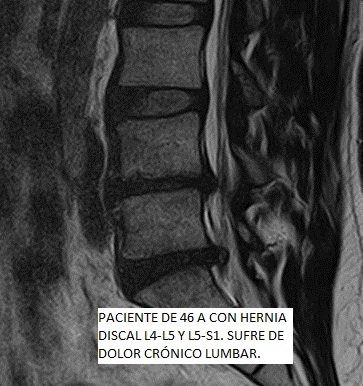

El mal d'esquena baixa o Dolor Lumbar, comunament té el seu origen en el funcionament incorrecte de diferents teixits de la regió lumbar incloent nervis, músculs, articulacions facetarias i discos intervertebrals. En la majoria dels casos, el dolor es produeix pel dany de diversos d'aquests teixits a la vegada, que funcionen com a peces d'un precís mecanisme on és necessària la integritat de cadascuna per a proporcionar una bona salut lumbar.

Les patologies del disc intervertebral es consideren de significativa contribució a la sensació dolorosa. Les hèrnies discals, protusions discals i l'artrosi, són les patologies degeneratives més comuns. La causa més freqüent de la Lumbàlgia o Dolor Lumbar és la degenerativa, associada a canvis biomecànics a la columna vertebral, resultant en un dany que pot arribar a severa intensitat i provocar una gran limitació de la nostra qualitat de vida.